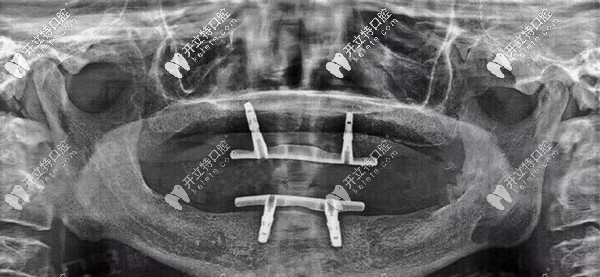

經(jīng)過一系列口腔拍片檢查后,陳叔口腔適合立得用技術(shù)做全口種植,當(dāng)時(shí)就和家人一起跟醫(yī)生確定了方案以及種植時(shí)間。